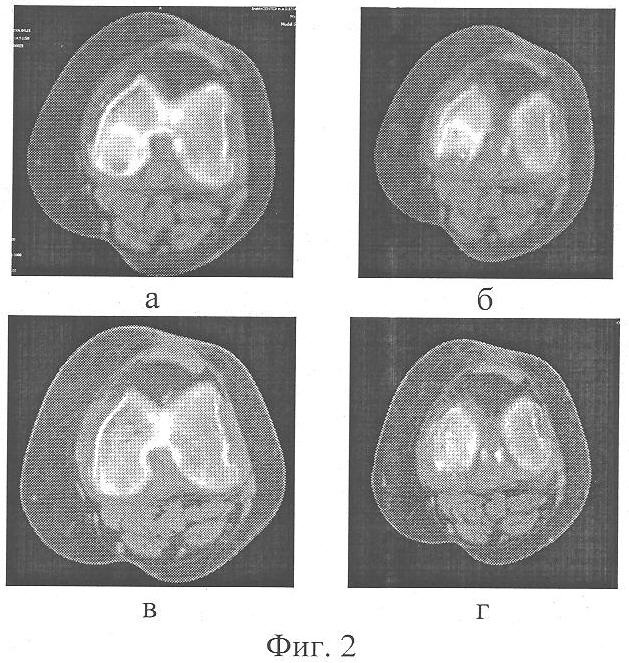

фиг.1 – Рентгенограмма левого коленного сустава пациентки Д., 61 года в прямой проекции: а) до лечения; б) в процессе туннелизации патологической зоны; в) через 6 месяцев после лечения;

При клиническом обследовании: варусное отклонение левой голени при стоянии на 5°, сгибательно-разгибательная контрактура левого коленного сустава 90-165°. При пальпации по внутренней поверхности правого коленного сустава отмечала болезненность. На рентгенограмме левого коленного сустава в прямой проекции – признаки гонартроза, характеризующие II стадию процесса, во внутреннем мыщелке левой бедренной кости костно-хрящевой дефект неоднородной структуры со склеротической границей вокруг очага деструкции и прерывистостью линии хрящевой поверхности мыщелка (Фиг.1а). На компьютерных томограммах патологический очаг локализован в заднем отделе внутреннего мыщелка бедренной кости. Дефект по площади составлял половину контактной поверхности мыщелка (Фиг.2а, б).

После обработки операционного поля антисептиком под эпидуральной анестезией со стороны неизмененного мыщелка бедренной кости через патологический очаг противоположного мыщелка бедра субхондрально введен костный перфоратор. При помощи толкателя из продольного паза костного перфоратора, перед его удалением, произведено выталкивание костной стружки, сформированной из неизмененной части мыщелка, в зону патологической перестройки. Аналогичным образом сформировано 10 параллельных между собой туннелей, проходящих через патологический очаг, с максимальным его охватом по объему (Фиг.1б). В проекции мыщелков бедренной и большеберцовой костей, где отсутствуют зоны патологической перестройки, фронтально выполнена веерная, субхондральная туннелизация суставных концов с образованием 6 туннелей в каждом мыщелке. Фронтально во взаимокосых направлениях субхондрально спицей в надколеннике сформировано 3 канала.

При рентгенологическом обследовании через 6 месяцев после операции (Фиг.1в) структура кости в проекции патологического очага перестройки однородная, непрерывность хрящевой поверхности восстановлена, склероз отсутствует. По данным компьютерной томографии коленного сустава – в заднем отделе внутреннего мыщелка бедренной кости отмечается восстановление структуры кости, структурно костный дефект активно восстанавливается (Фиг.2в, г).